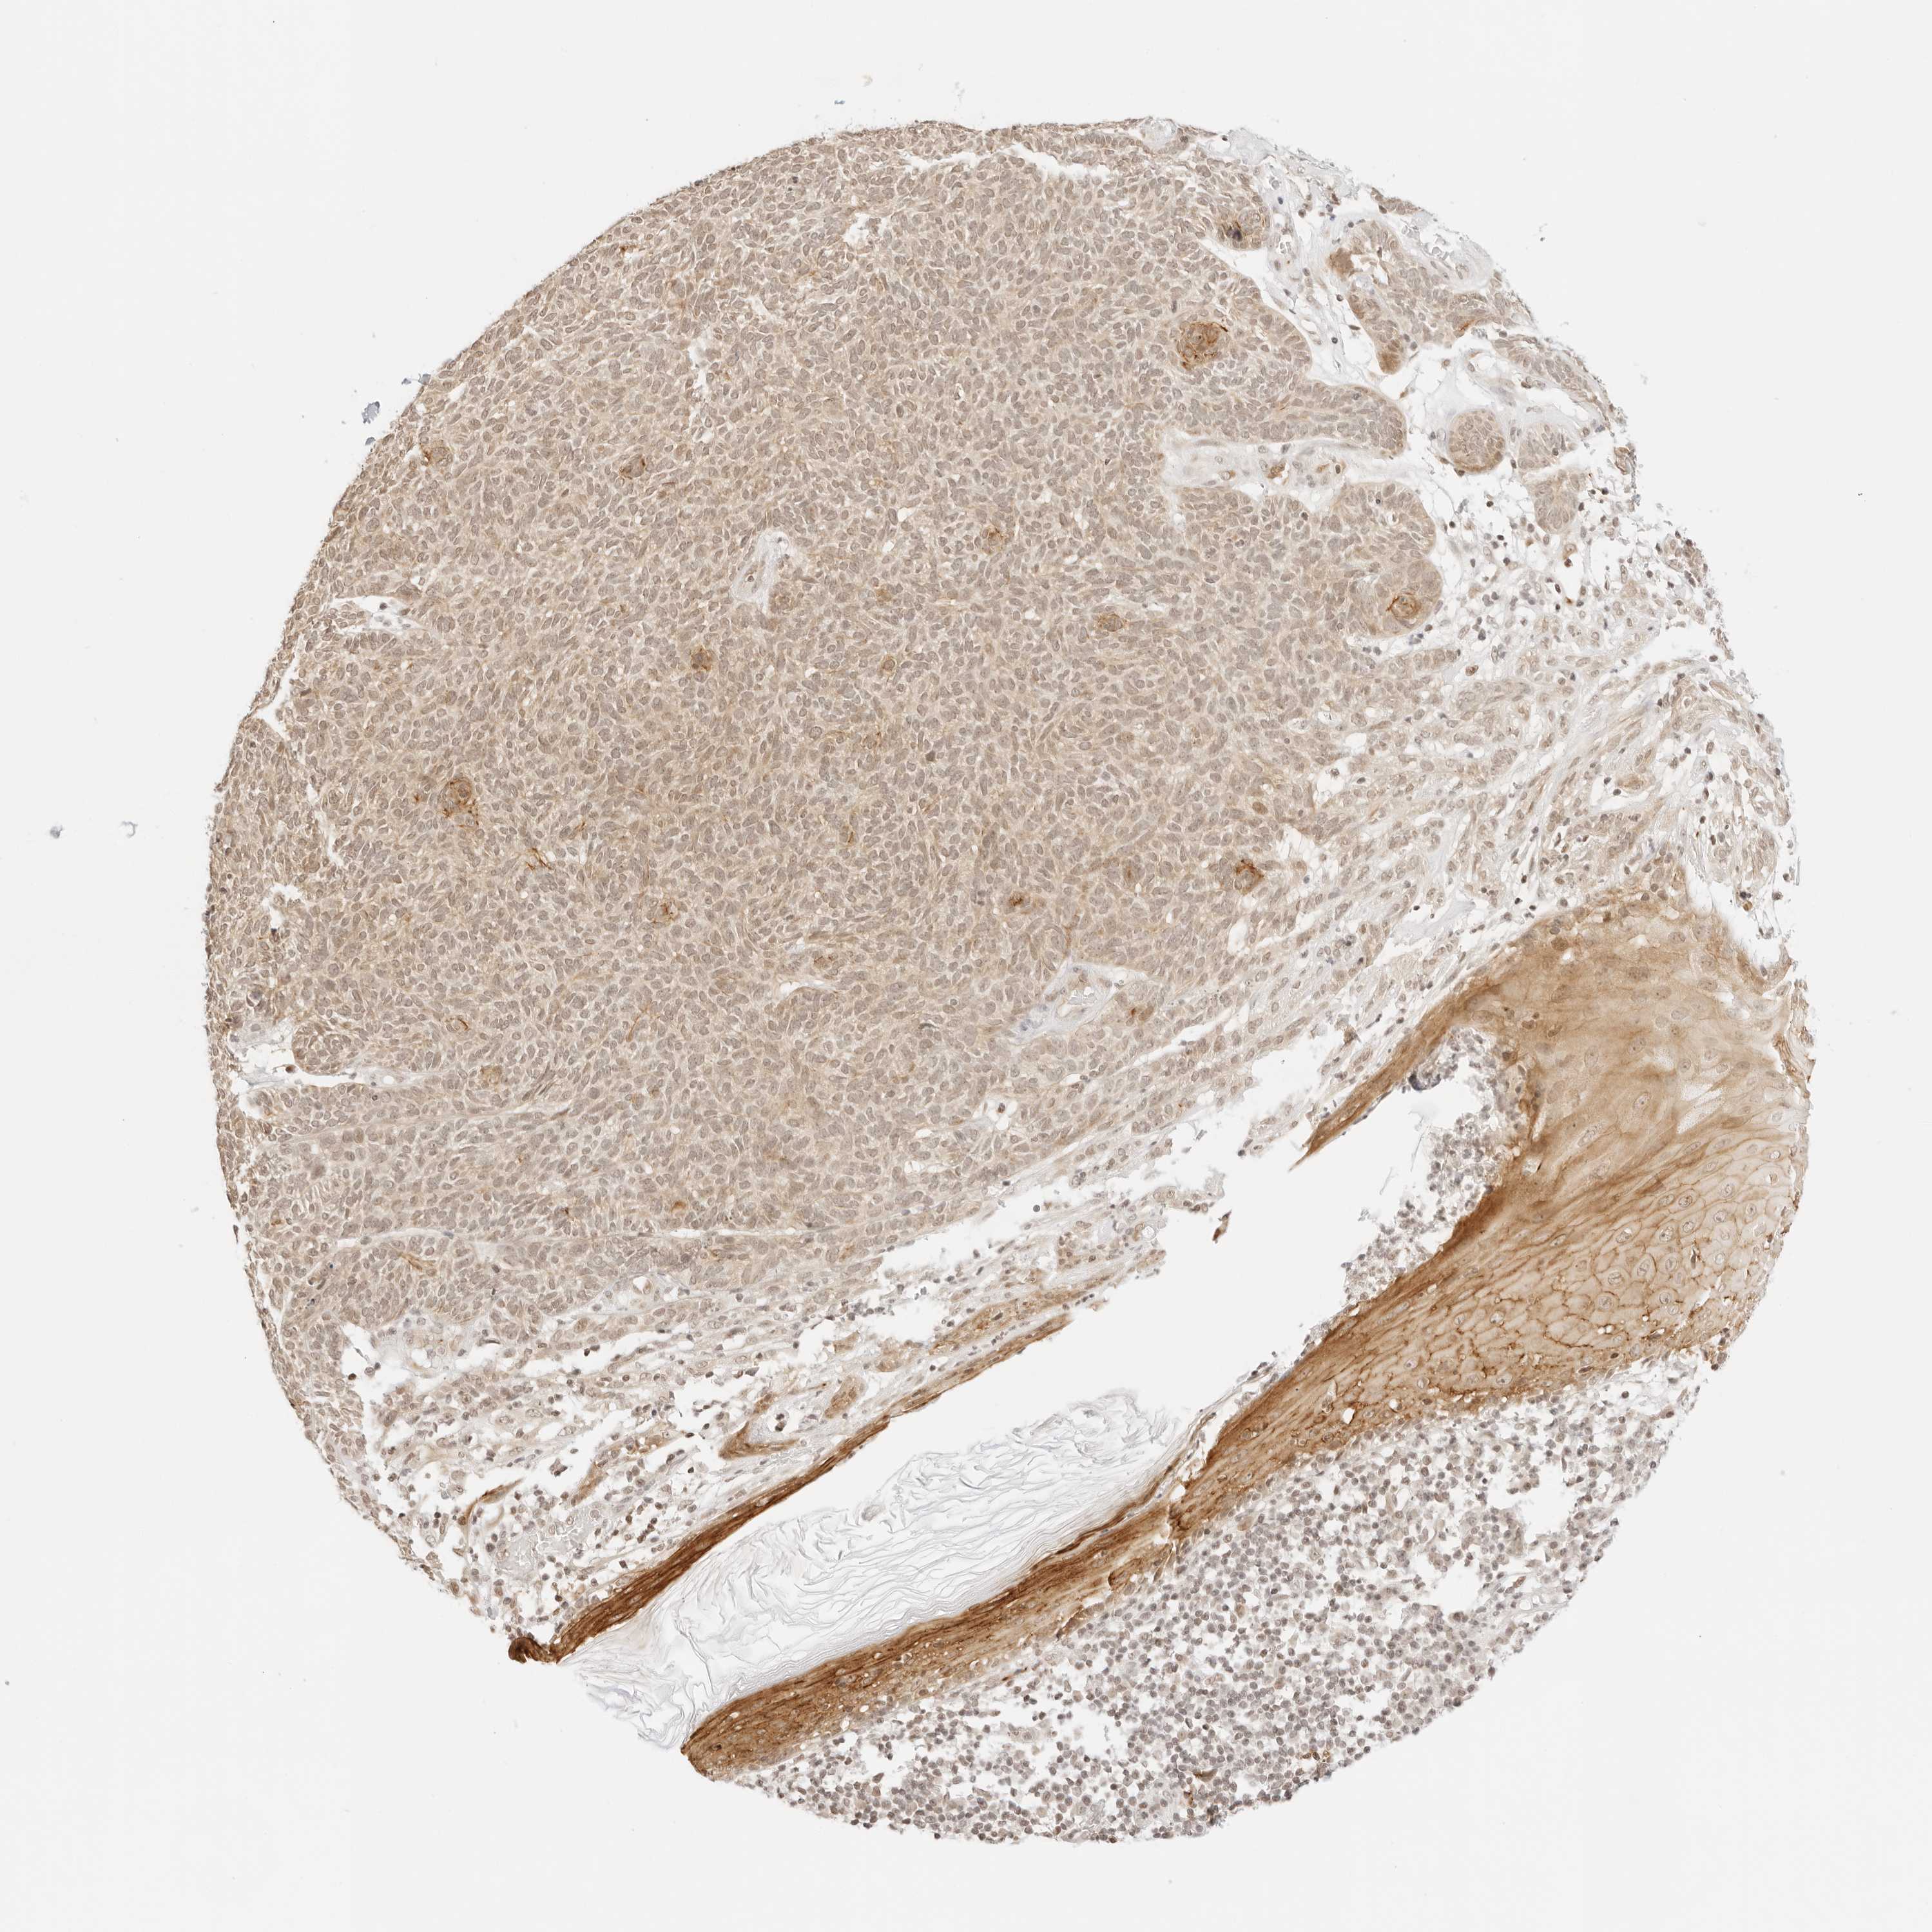

SKIN CANCER - Protein expressioni

A mouse-over function shows sample information and annotation data. Click on an image to view it in a full screen mode. Samples can be filtered based on level of antibody staining by selecting one or several of the following categories: high, medium, low and not detected. The assay and annotation is described here.

Each image is clickable and will lead to virtual microscopy that enables deeper exploration of all samples and also displays staining intensity scores, fraction scores and subcellular localization as well as patient and tissue information for each sample.

Antibody HPA028386

Staining

High

Medium

Low

Not detected

Intensity

Strong

Moderate

Weak

Negative

Quantity

>75%

75%-25%

<25%

None

Location

Nuclear

Cytoplasmic/membranous

Cytoplasmic/membranous,nuclear

Squamous cell carcinoma, metastatic, NOS